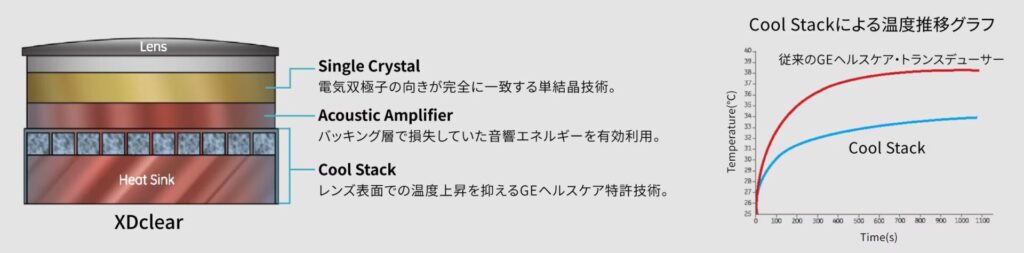

この機器は浅部から深部までを鮮明に描出することが可能なXDclear、小さな異変も見逃さない検査の基盤となるイメージパフォーマーとなるcSoundが導入されており、従来の心臓超音波検査機器と比較して、より鮮明に心臓の描出ができるようになっています。

2画面画像比較View

過去画像をタッチパネル上に表示し、現在スキャン中の画像と比較しながら検査が可能となり、よりスピーディな評価が可能となっています。

このようにVividは心臓の検査により強い超音波検査機器であり、以前の機器よりも心臓の状態をより詳細に把握することが可能となります。そのため、評価の難しい心臓の病気や心臓病の進行度合いなどをより詳しく把握することが可能となりました。